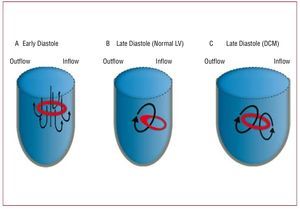

Figure 11. Simplified sketch of the dynamics of the left ventricle (LV) vortex ring during diastole. (A) A symmetric vortex ring generates around the mitral jet during early filling (see Figure 10A). (B) In a normal ventricle, the part of the vortex ring that is closer to the posterior wall of the LV decays due to viscous friction with the wall. As a result, the vortex ring becomes asymmetric during late diastole, creating a large single vortex that redirects blood from the inflow to the outflow of the ventricle (see Figure 10B and Figure 12A). (C) In a dilated ventricle, the posterior part of the vortex ring does not decay as fast as in the normal case. Consequently, the vortex ring does not lose its symmetry during late diastole, leading to additional counter rotating vortices contrary to the natural blood redirection in the LV (see Figures 12B and 12C). DCM indicates dilated cardiomyopathy.

Our current understanding of the hemodynamic irregularities that occur in patients with altered diastolic function is beginning to benefit considerably from clinical pilot studies based on the non-invasive characterization of the LV diastolic vortex. Ishizu et al159 have found that the size of this vortex increases by approximately 2 factors in patients with pseudonormalized transmitral flow patterns. By comparing PCMR data from 17 normal LVs to 1 dilated ventricle, Bolger et al157 have concluded that the fraction of mechanical energy that is stored by the LV vortex may be lower in patients with dilated cardiomyopathy (DCM). More recently, Hong et al141 have shown that the strength, size and temporal pulsatility of the diastolic vortex are lower in patients with DCM than in healthy volunteers. Recent studies by one of our groups161-163 suggest that the hemodynamic irregularities observed in DCM patients may be caused by the slower loss of symmetry of the early diastolic vortex ring, as opposed to the rapid loss of symmetry observed in normal LVs (Figure 10 and Figure 11). The physical argument for this behavior is that the posterior part of the vortex ring is farther from the wall in a dilated LV than in a normal LV (Figure 11C). Therefore, this part of the ring is subject to less viscous dissipation and does not decay as rapidly as in a normal LV. This picture is supported by Figure 12, which shows blood velocity maps in 1 healthy human LV and 2 dilated ones during late diastole. These maps indicate that only 1 clockwise vortex corresponding to an asymmetric vortex ring remains in the healthy LV (Figure 11B). However, additional counter-rotating vortices corresponding to a symmetric vortex ring persist in patients with DCM (Figure 11C). Counter-rotating vortices have been associated with higher energy losses in numerical simulations.166 Furthermore, they oppose the efficient redirection of blood from the mitral valve to the aortic valve that occurs naturally in healthy hearts. Figure 12 suggests that the size and circulation of the abnormal vortex, relative to those of the physiological one, increase with the severity of the disease. These results have led us to hypothesize that altered flow patterns may cause higher power requirements during early ejection, thereby reducing the pumping efficiency of the LV.